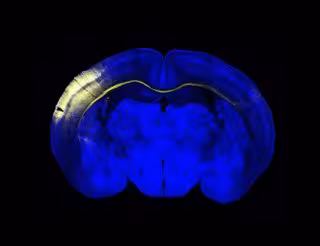

Sección horizontal del cerebro del ratón. Un grupo de neuronas de la corteza iluminadas en amarillo extienden sus axones a través del cuerpo calloso para conectar con el hemisferio contralateral.

Los dos hemisferios cerebrales procesan información distinta y la conexión entre ambos es esencial para la realización de las funciones más complejas, como la verbalización de la información sensorial, la interpretación de un discurso dentro de su contexto o las relaciones sociales. Ambos hemisferios están conectados mediante el cuerpo calloso, "una autovía de intercambio de información" que se desarrolla durante la infancia y la adolescencia.